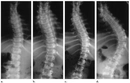

Her bir tür, farklı tedavi yaklaşımları gerektirebilir. İdiyopatik skolyoz, genellikle ergenlik döneminde ortaya çıkar ve tedavi edilmediğinde ciddi sorunlara yol açabilir. Skolyozun TanısıSkolyozun tanısı genellikle fizik muayene ve görüntüleme yöntemleri ile konur. Doktor, hastanın duruşunu değerlendirir ve gerekirse röntgen çekimi yapar. Röntgen, omurganın eğilimini ve açılarını belirlemeye yardımcı olur. Skolyoz Tedavi YöntemleriSkolyoz tedavisinde kullanılan başlıca yöntemler şunlardır:

Fizik Tedavi ve Egzersiz: Fizik tedavi, skolyozun ilerlemesini durdurmak ve postürü düzeltmek için önemli bir rol oynar. Hastalara özel egzersiz programları uygulanır. Bu programlar, kas gücünü artırmayı ve esnekliği geliştirmeyi hedefler. Ortez Kullanımı: Ortezler, omurganın düzeltilmesine yardımcı olmak için kullanılan cihazlardır. Özellikle büyüme çağındaki çocuklar için etkili olabilir. Ortezlerin kullanım süresi, skolyozun şiddetine bağlı olarak değişir. Cerrahi Müdahale: Eğer skolyoz ilerliyorsa ve diğer tedavi yöntemleri yeterli olmuyorsa cerrahi müdahale gerekebilir. Cerrahi işlemler genellikle omurganın düzeltilmesi ve stabilizasyonunu hedefler. Bu tür bir müdahale, hastanın yaşına, genel sağlık durumuna ve skolyozun şiddetine göre planlanır. SonuçSkolyoz tedavisi, bireysel ihtiyaçlara göre özelleştirilmelidir. Tedavi yöntemleri arasında fizik tedavi, ortez kullanımı ve cerrahi müdahale gibi seçenekler bulunmaktadır. Erken tanı ve uygun tedavi, skolyozun yönetiminde kritik öneme sahiptir. Her birey için en uygun tedavi yönteminin belirlenmesi, uzman bir hekim tarafından yapılmalıdır. Ek BilgilerSkolyoz hastalarının takip edilmesi ve düzenli kontrollerin yapılması, tedavi sürecinin etkinliği açısından önemlidir. Ayrıca, skolyozun psikolojik etkileri de göz önünde bulundurulmalıdır. Hastaların duygusal destek alması, tedavi sürecini olumlu yönde etkileyebilir. Skolyoz ile ilgili daha fazla bilgi ve destek almak için uzman sağlık profesyonellerine başvurulması önerilmektedir. |